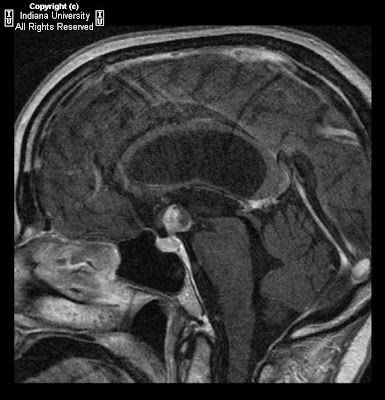

Figure 9, Figure 10, and Figure 11: Diffusion weighted images demonstrate areas of high signal and restricted diffusion in the midbrain, splenium of the corpus callosum and high right frontal white matter.